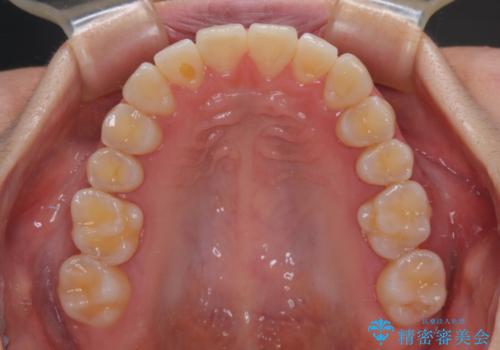

1年弱で治療方針を変更したため、治療期間は長くなりましたが、スペースは無事に閉じ、咬合の違和感なく仕上げることができました。

ただし、両方の臼歯部は理想的な咬合とは言えないため、咬合による歯の外傷を防ぐため、就寝時にはマウスピースを継続使用するようお願いしております。